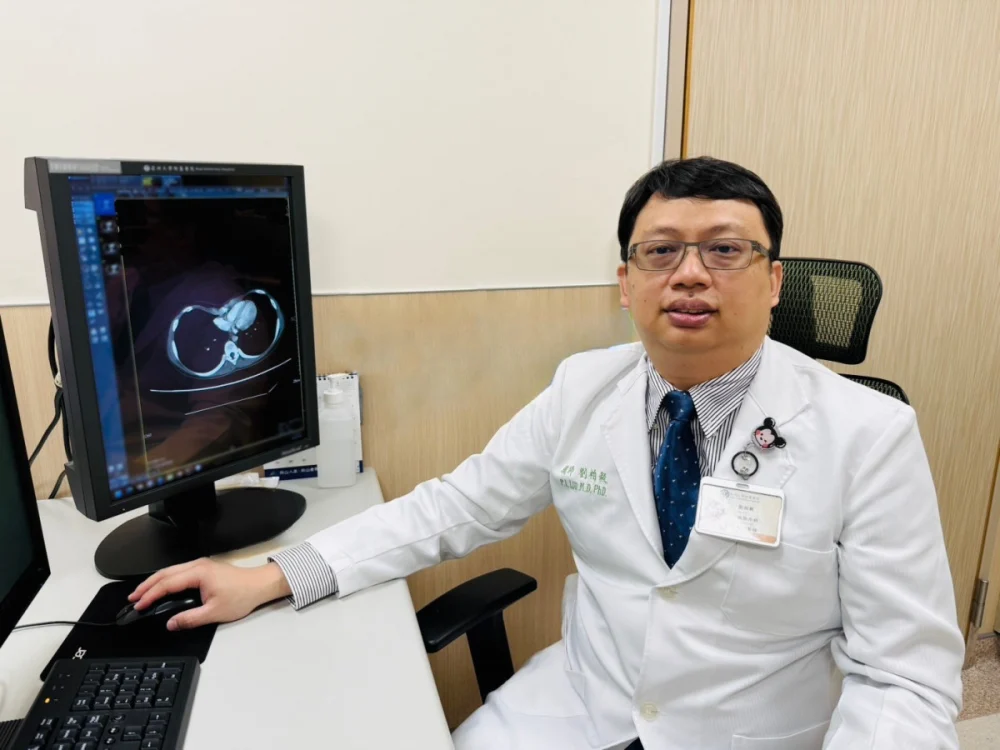

揮別攝護腺癌 「海扶刀」精準定位消融癌細胞

記者季大仁/新竹報導東元醫院泌尿外科戴順慶醫師利用「海扶刀(HIFU)高強度聚焦超音波微創手術」幫助多名攝護腺癌病人,揮別早期攝護腺癌症陰霾。攝護腺癌呈現年輕化,正值壯年的病人而言,如何在根除癌症的同時保留生活品質是關鍵。東元綜合醫院泌尿外 …